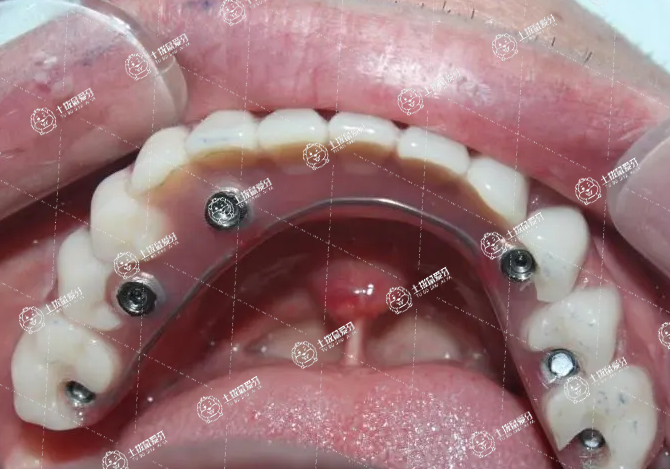

全口種植牙修復是在無牙頜患者牙槽嵴內(nèi)植入種植體,在種植體上部再進行義齒修復。全口種植牙修復的優(yōu)點是固位性好、穩(wěn)定性好、減少由于義齒不穩(wěn)帶來的壓痛感。缺點是手術時間長、費用高。